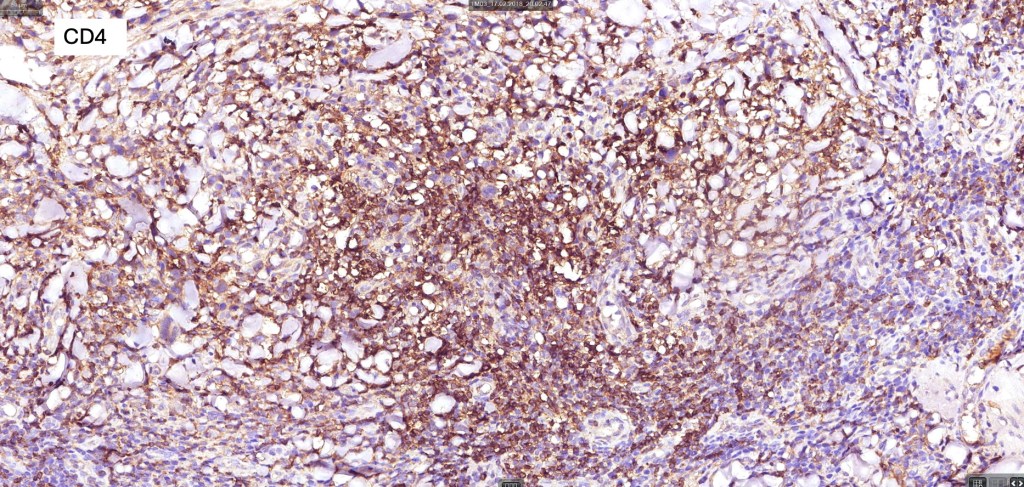

Immunohistochemistry

•Clonal T-cell receptor rearrangement is supportive but not diagnosis of mycosis fungoides as it may be seen in a variety of inflammatory dermatoses

•TCRβ, CD45RO, IL-2R, CLA, CD25, CD2, CD3, CD4, CD5, CD7 +ve

•Much less often CD8+ve

•Variable loss of CD5 (supports the diagnosis) & CD7 (not so helpful as also seen in inflammatory dermatoses)

.TCRγ, TIA, granzyme & EBER -ve